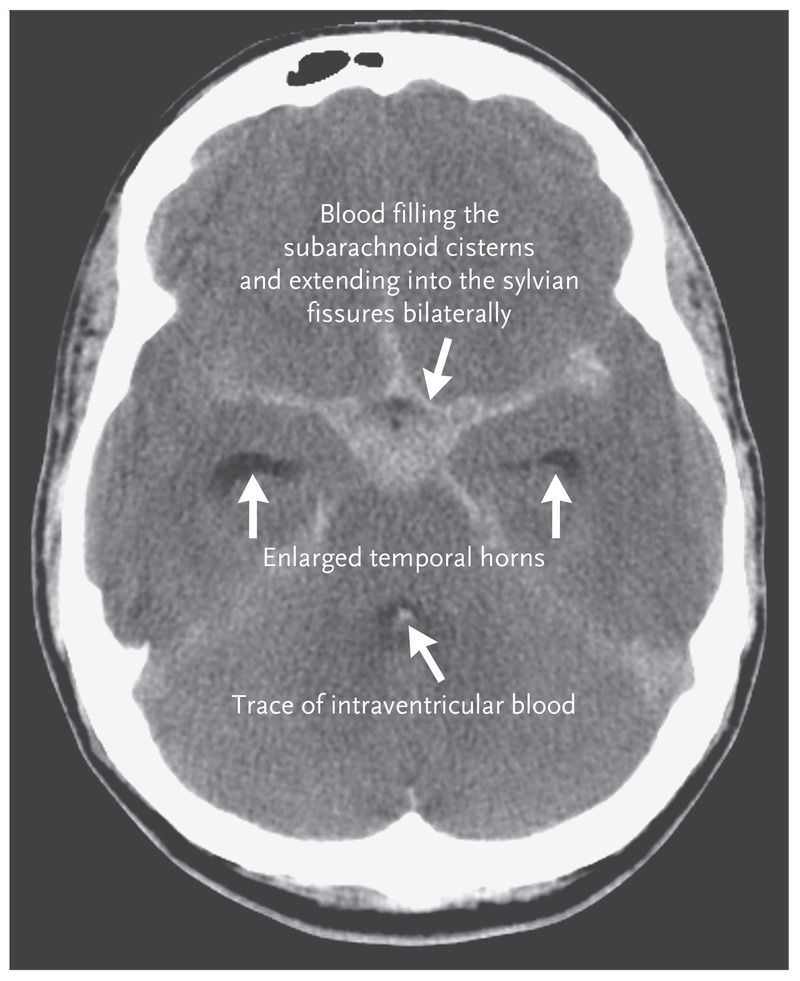

What causes a subarachnoid hemorrhage?

What does it look like on an x-ray?

Rupture of one of the blood vessels supplying the CNS. All of the major blood vessels supplying the CNS pass through or course in the subarachnoid space.

Spiderweb shape